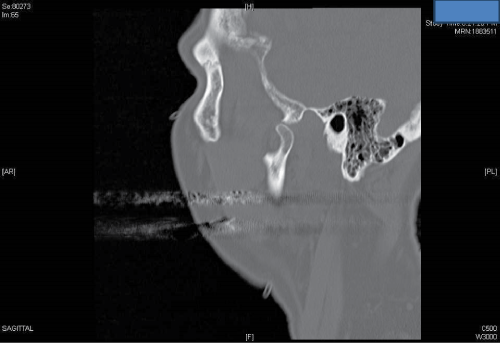

A C.T. scan revealed left condylar head subluxation and right condylar head fracture with medial displacement. The margins of the fracture were fresh according to the radiologist’s report, which excludes the possibility of a pre-existing fracture (Figure 2a,2b).